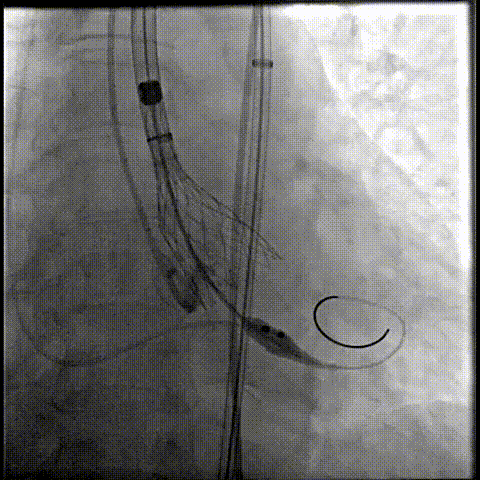

23球囊后扩

最终造影形态位置良好,轻微瓣周漏

术后压差降为0mmHg